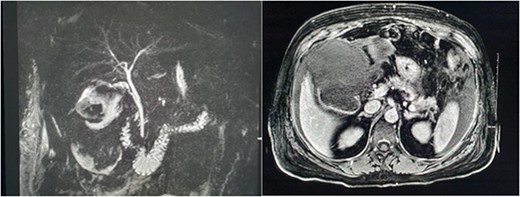

Magnetic resonance imaging (MRI) of the liver and magnetic resonance cholangiopancreatography (MRCP) were performed in the following days, which demonstrated a frank rupture of the gallbladder and a patent biliary tree (Fig. 3). After a few more days, the patient became peritonitic and a further CT was performed. This demonstrated a moderate volume of peritoneal free fluid and haematoma in the gallbladder fossa (Fig. 4). Ultrasound-guided drainage of peritoneal fluid was performed producing bilious fluid. ERCP was performed, which demonstrated ongoing leak from the gallbladder fossa (Fig. 5) and allowed placement of a covered biliary stent to divert flow away from the cystic duct.

MRCP and post contrast MRI images demonstrating the wide mouthed frank disruption of gallbladder wall.